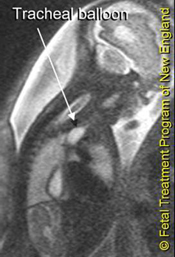

Fetal intervention to prevent pulmonary hypoplasia—the main danger associated with congenital diaphragmatic hernia (CDH)—began in the 1990s with open fetal surgery. As in utero techniques evolved, open fetal surgery was replaced by fetal tracheal occlusion, which has been shown to result in accelerated growth of hypoplastic lungs. In the last decade, research has focused on further understanding the mechanisms involved in accelerated lung growth following fetal tracheal occlusion. Occlusion can now be performed through a single entry port—a technique developed through our program. This technique uses an inflatable and detachable balloon to occlude the fetal trachea.

The multicentric Eurofoetus study showed that fetal endoscopic tracheal occlusion produced positive results in severe cases of CDH: fetuses that were identified as having a survival rate of less than 10 to 40 percent, despite all current methods of postnatal therapy. In this group, endoscopic tracheal occlusion increased the survival rate to 50 to 80 percent. We believe that for babies with severe CDH, this treatment technique will allow enough accelerated lung growth for an intermediate or good prognosis, and a predicted survival rate of greater than 50 to 65 percent.